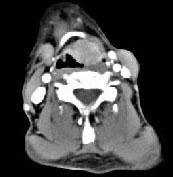

问题 男,53岁,咽部不适半年余,近两个月感咽部疼痛,声嘶,CT如图所示,应诊断为()

选项 A.乳头状瘤 B.喉癌 C.梨状窝癌 D.喉肉芽肿 E.喉部纤维瘤

答案 B